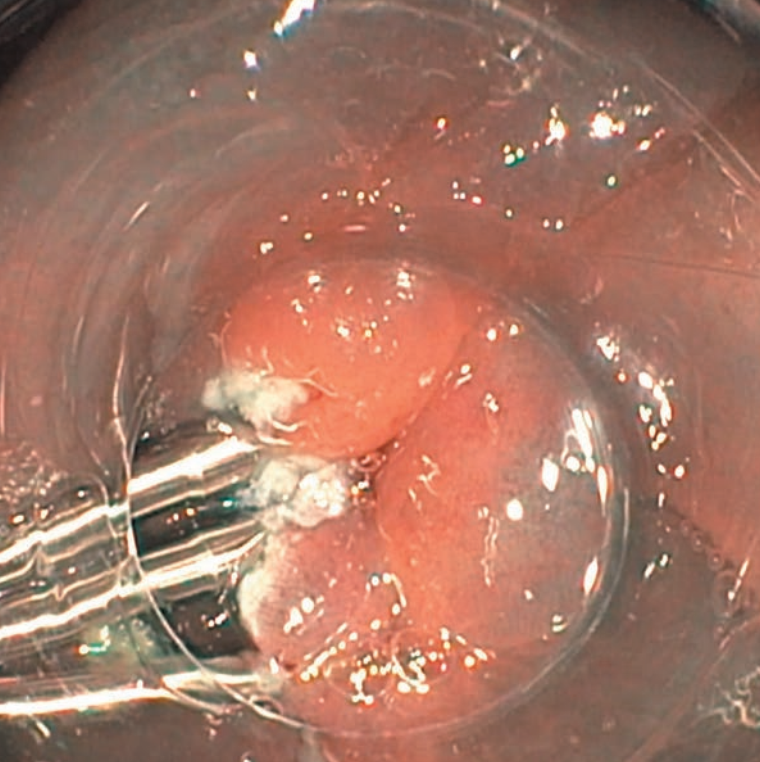

EMR of LST G-NM (0-Is) type lesion, located in the transverse colon, with intense fibrosis in the central part, size – 35 mm. The procedure performed mostly in water immersion (SnareMaster Plus 15 mm).

4Performing a complete circular resection of the edges of the lesion facilitates „mobilisation” and removal of the central part of the lesion. Fibrosis in the submucosal layer is usually most significant in this part of the lesion (Fig. 13B). Before removing the central part of the lesion, I make sure that the marginal resection is complete (Figs. 8A-10A).

5Fibrosis in the submucosal layer, may be the cause of the non-lifting sign. To remove non-lifting lesion fragments, I use a stiff, thin wire snare (Fig. 11A, Fig. 11B, Fig. 12B). Electrocoagulation is usually necessary to remove these fragments.